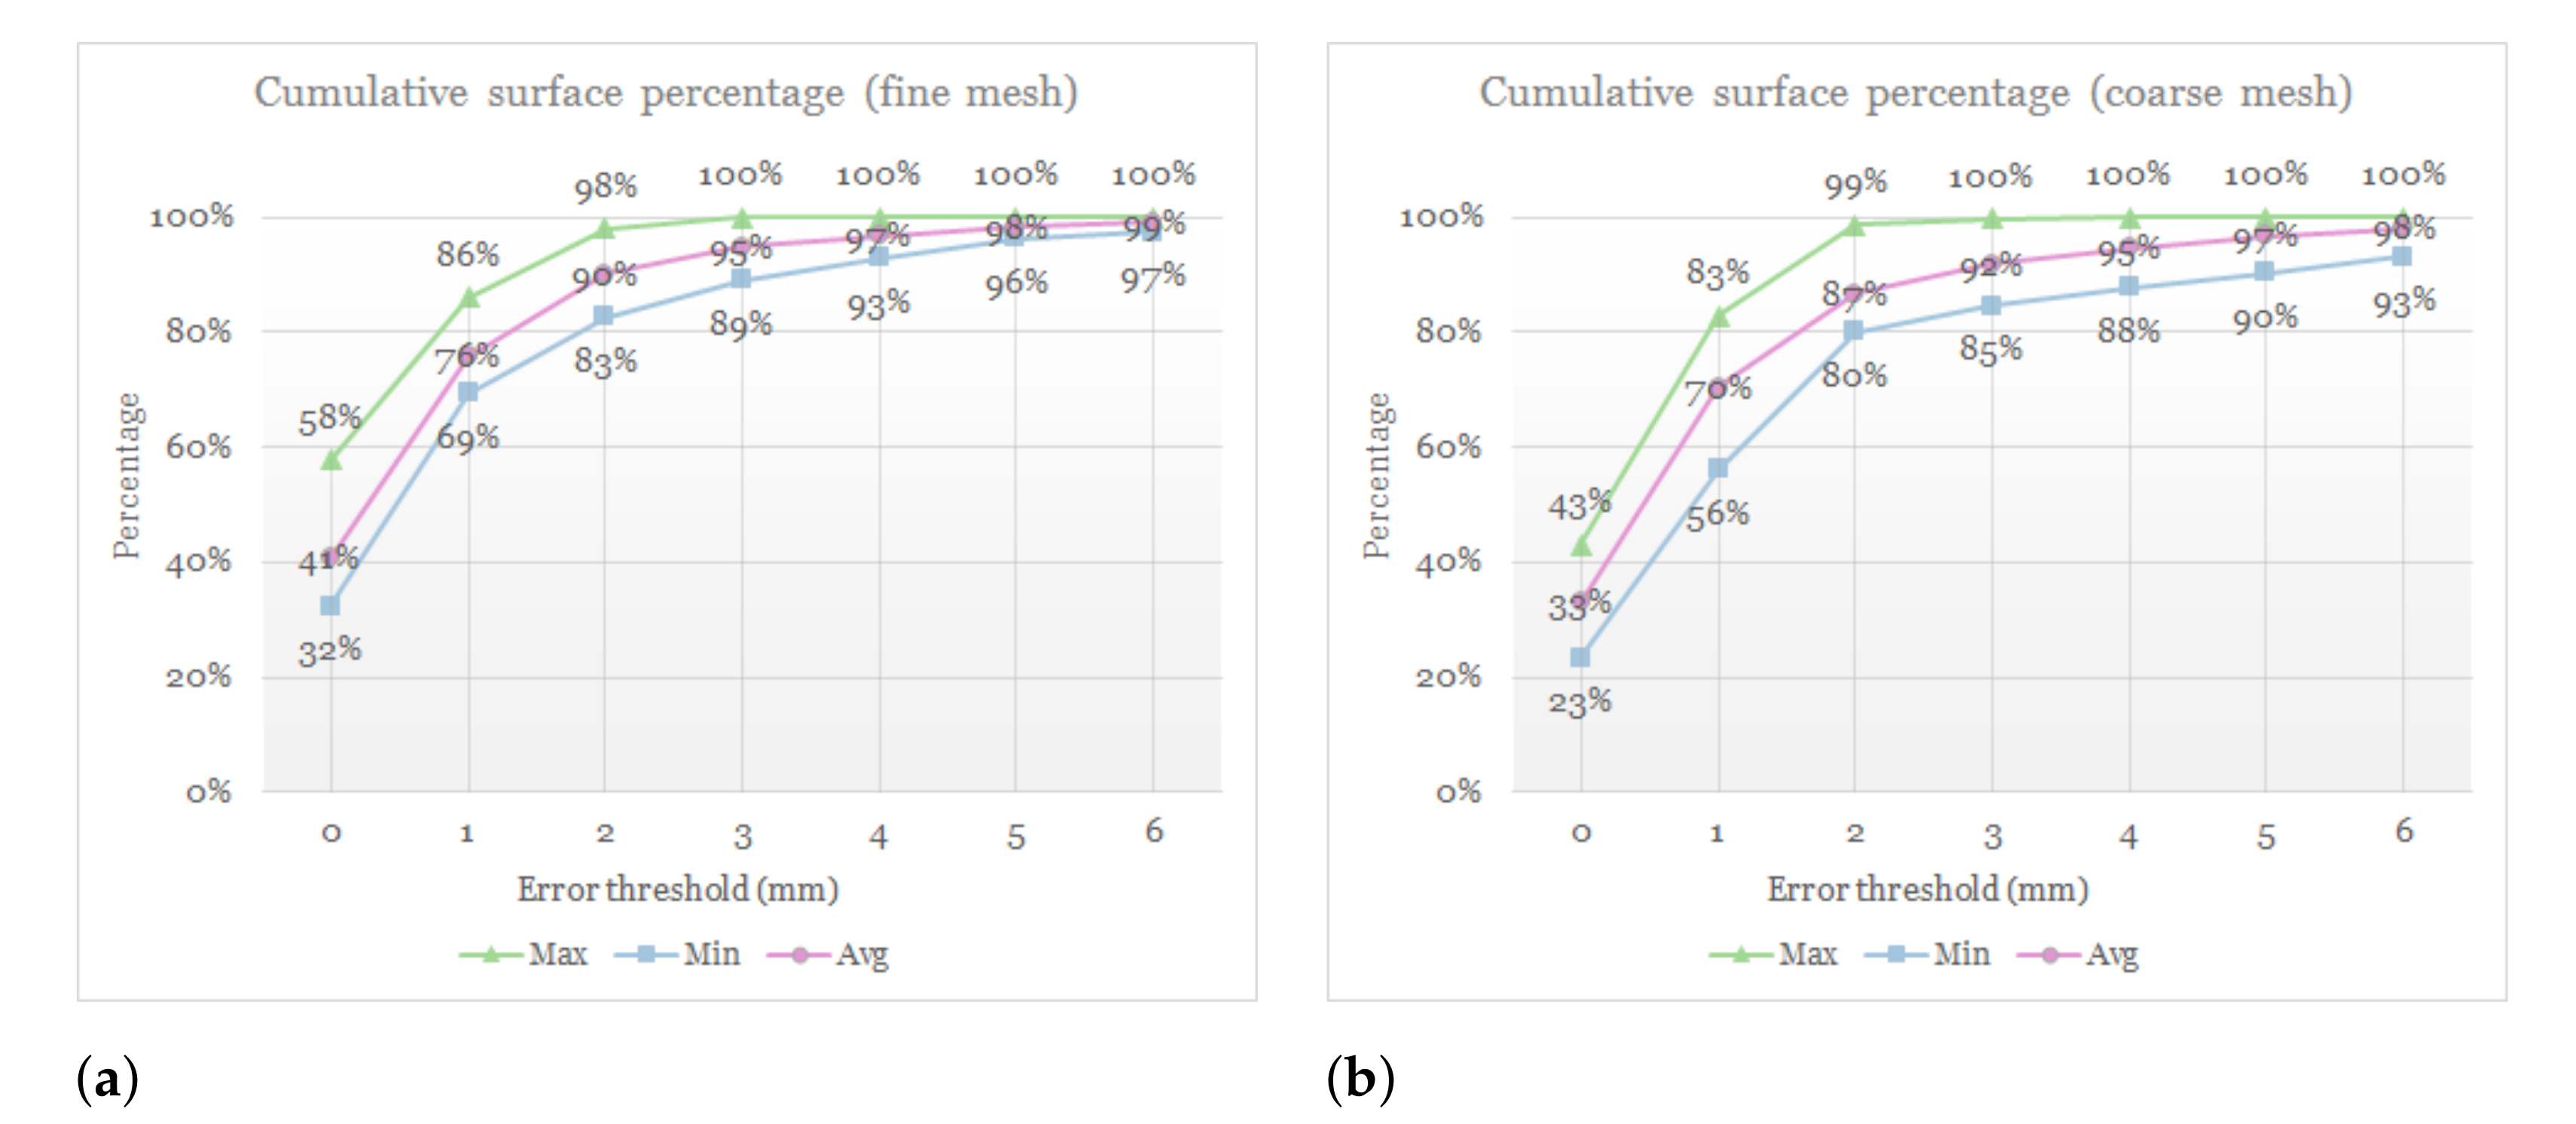

3.3. Simulation Error and Performance

4.3. Comparison of Fine and Coarse Meshes

5. Conclusions